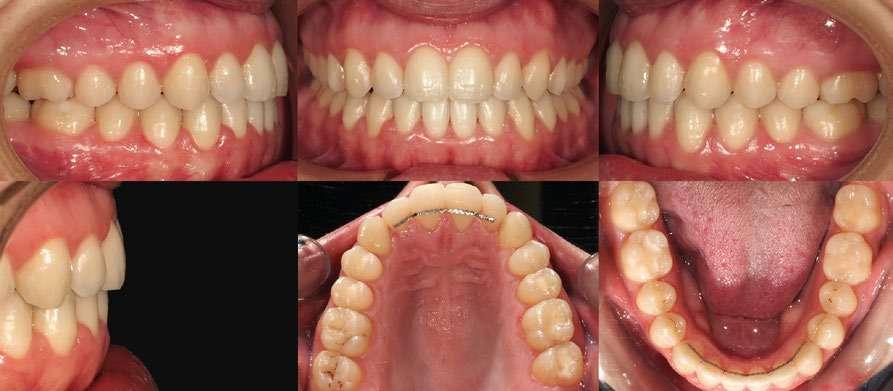

Resultados del tratamiento

La duración total del tratamiento fue de 17 meses, obteniendo los siguientes resultados: (Fig. 12, 13, 14):

1. La expansión dentoalveolar en ambas arcadas fue posible mediante la corrección de los torques negativos en las piezas posteriores, lo que también supuso una mejoría muy notable en la estética de la sonrisa.

2. El cierre de la mordida abierta se llevó a cabo mediante la extrusión de los incisivos superiores (mejorando así el arco de la sonrisa) y el proceso denominado “adaptación transversal posterior”.

3. La corrección de los torques en los incisivos tanto superiores como inferiores (especialmente 11-21) se pudo conseguir mediante el empleo del Sistema Damon Ultima y el uso de los arcos Overdrive (.019 x .0275 y .021 x .0275).

4. El centrado de líneas medias se logró mediante el empleo de elásticos asimétricos durante las diferentes fases del tratamiento.

Fig. 12: Fotografías intraorales del final del tratamiento.